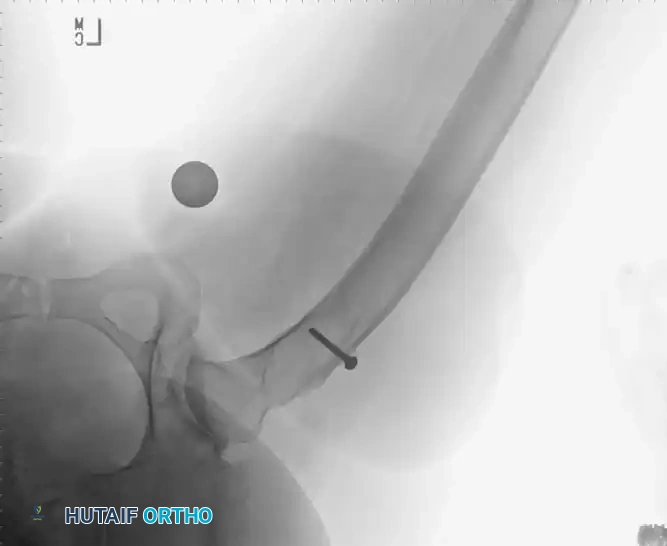

Surgical Technique and Prior Graft Management

Upon capsulotomy, the surgeon will often encounter a highly hyperemic capsule and profound synovial proliferation. A large synovial effusion is common and should not immediately be mistaken for infection, though routine cultures are prudent. Meticulous hemostasis is required.

Pitfall: If the patient has previously undergone a cortical bone grafting procedure (e.g., free or vascularized fibular graft), the intramedullary portion of the graft must be completely excised. Conventional broaches will deflect off the hard cortical graft, leading to varus malpositioning and undersizing of the femoral component.

To safely remove prior grafts, the surgeon should utilize a high-speed burr and flexible reamers. Intraoperative fluoroscopy with the broach in place is highly recommended to ensure complete graft removal, proper alignment, and optimal cortical contact.

Radiographic Case Examples: Osteonecrosis and Complex Femoral Reconstructions

Use of a high-speed burr to clear the intramedullary canal of sclerotic graft remnants.

Fluoroscopic confirmation of proper broach alignment after graft removal.

Final seating of a cementless femoral stem in optimal neutral alignment.